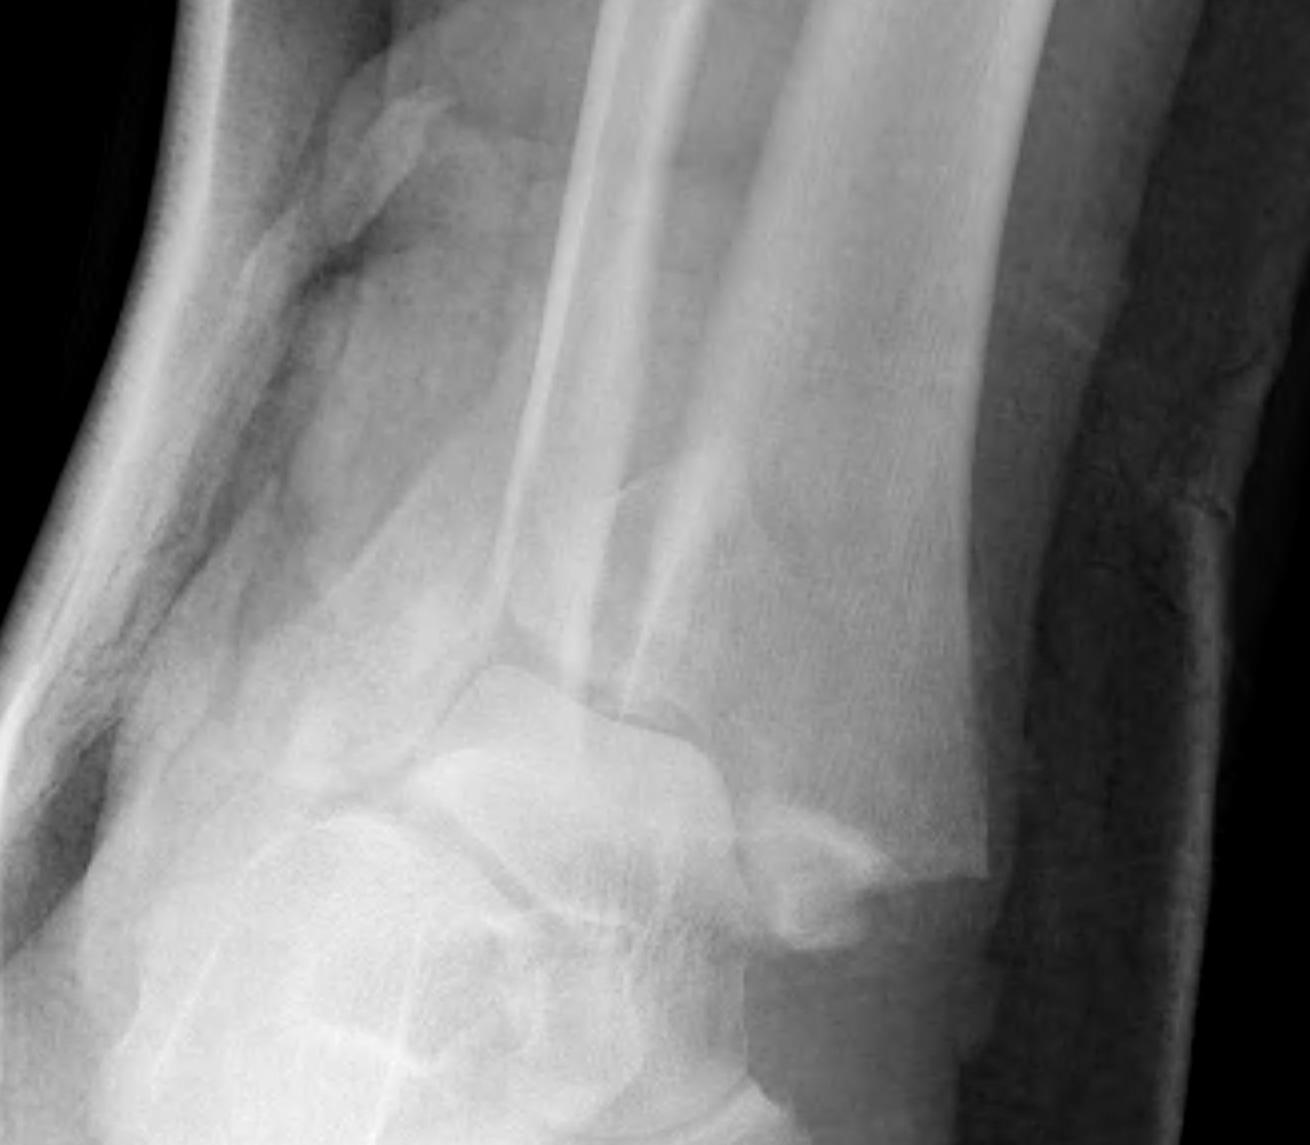

Dislocated ankle joint with large posterior malleolus

Articular incongruency

Posterior malleolus and syndesmotic injury